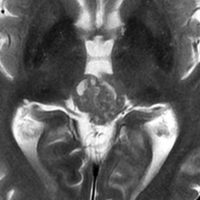

無症状で発見された40代女性です。1年半の経過観察で増大傾向を示し,閉塞性水頭症となってきました。形が不整形で右視床に食い込んでいるのでPPTIDだと考えて開頭手術をしました。手術所見でも右視床に深く食い込み中脳視蓋の周囲に回り込むように張り付いていました。松果体細胞腫が視床浸潤する事はほとんどなくPPTIDの特徴です。初期の病理確定診断は,PPTID grade II/III (グレード2に近いもの)でしたが,その後,グレード3と訂正されました。グレードが2か3かという判断は,病理診断医にとっても極めて難しいものです。